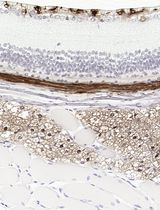

• Compatible with diagnostic IHC/IF markers (pan-CK, CK19, p63, Ki-67, p53) across cancer organoids.

The major strength of this approach lies in its ability to reliably preserve both structural integrity and histological detail, which are essential for downstream applications such as H&E staining, immunohistochemistry, and immunofluorescence. Although the method involves steps that may appear harsh—such as drying and the addition of warm agarose—and FFPE processing can impose certain limitations, molecular analyses that are highly sensitive to fixation stress may be restricted. Nevertheless, this protocol effectively supports morphological assessment and protein-level studies. In our validation, we confirmed the expression of cancer diagnostic markers such as CK19, pan-CK, and P53 and further demonstrated that marker expression relevant to subtype classification could be evaluated using tissue proteomics–based analysis [9,19–21]. Overall, this protocol provides a practical and robust method for generating high-quality FFPE organoid slides, making it well-suited for cancer research, biomarker evaluation, and translational applications in personalized medicine.